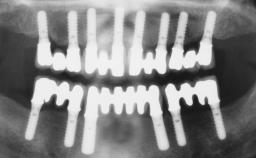

Immediate Loading of Four Implants in the Mandible and Final Restoration with a Full-Arch Metal Framework FDP

Pedro Tortamano, Luiz Otávio Alves Camargo

A fully edentulous 65-year-old woman was referred to our clinic for esthetic and functional dental rehabilitation. The patient presented with inadequate complete maxillary and mandibular prostheses, insufficient vertical dimension, and extensive tooth wear. The clinical examination and anamnesis showed no local or systemic contraindications, no signs or symptoms of bruxism, and an absence of smoking habits. The treatment proposed was implant placement in the mandibular interforaminal area and immediate loading with a fixed definitive prosthesis. A removable mucosa-supported complete prosthesis was indicated for the upper jaw, since its bone structure offered satisfactory retention and the financial condition of the patient disfavored a full-mouth implant-supported rehabilitation.

# of Implants 4

Type of Implants One-Piece

Loading Protocol Immediate

Retention Screw-retained, with 4 or more splinted implants Screw-retained, with 4 or more splinted implants